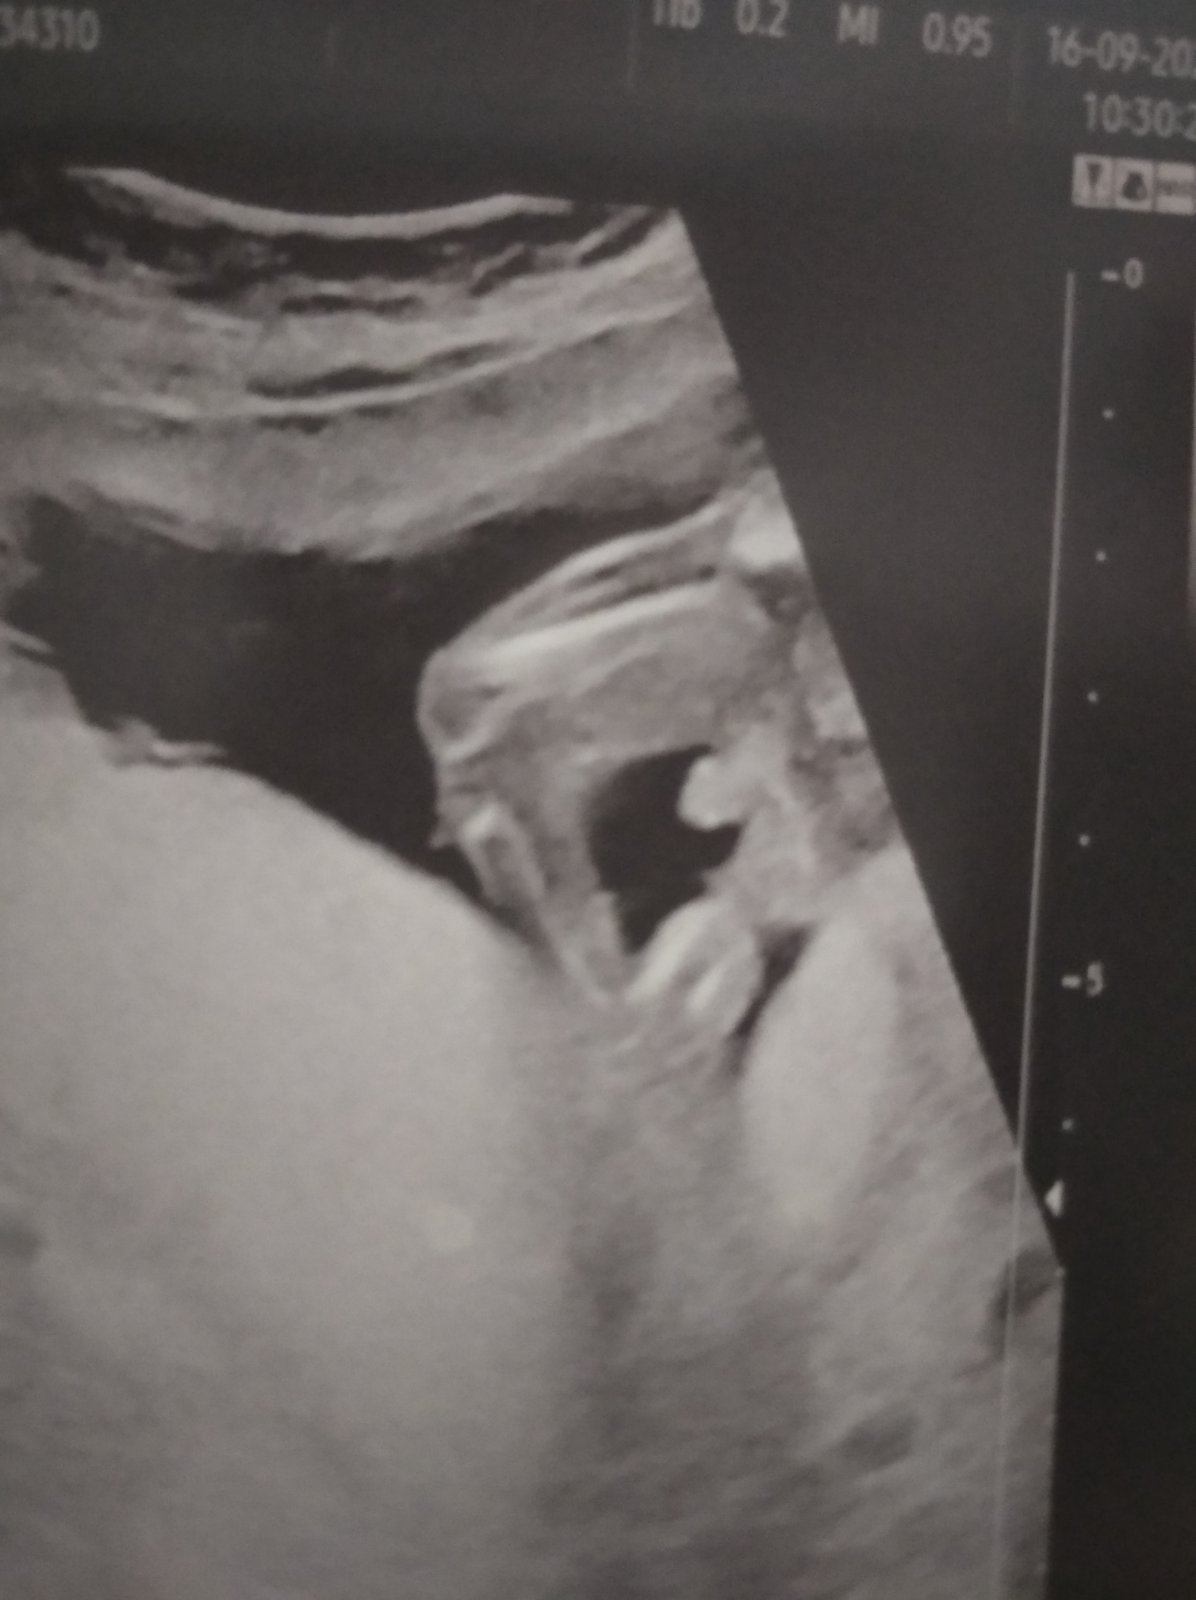

doktorka mi na běžné kontrole řekla, že podle této fotky je to kluk. Fotka je zachycena zepředu, tedy ne klasicky zespodu mezi nohama plodu, ale zde je zachycen podle doktorky pindík pod bříškem plodu. Plod byl natočen zepředu - tedy obličej a bříško směřovalo k fotce. Když koukala zespodu mezi nohy, žádný pindík vidět ale nebyl a sama řekla, že takhle to vypadá na holku, ale pak viděla, že něco trčí pod bříškem mezi nožkama a prej 100% kluk. Ultrazvuk je ze 17. tt.

Je možné, že to je vážně kluk, když zespodu to vypadalo na holku?